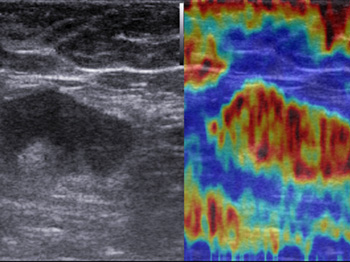

- Компрессионная эластография

- Эластография сдвиговой волны

Компрессионная эластография. Эта методика выявления опухоли, построенная на анализе отличий модулей продольной упругости, была принята в качестве общего стандарта и применяется для детального исследования поверхностно расположенных органов. С ее помощью в